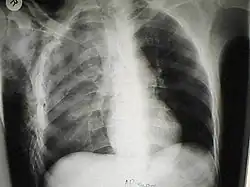

A chest X-ray of a right sided pulmonary contusion associated with flail chest and subcutaneous emphysema